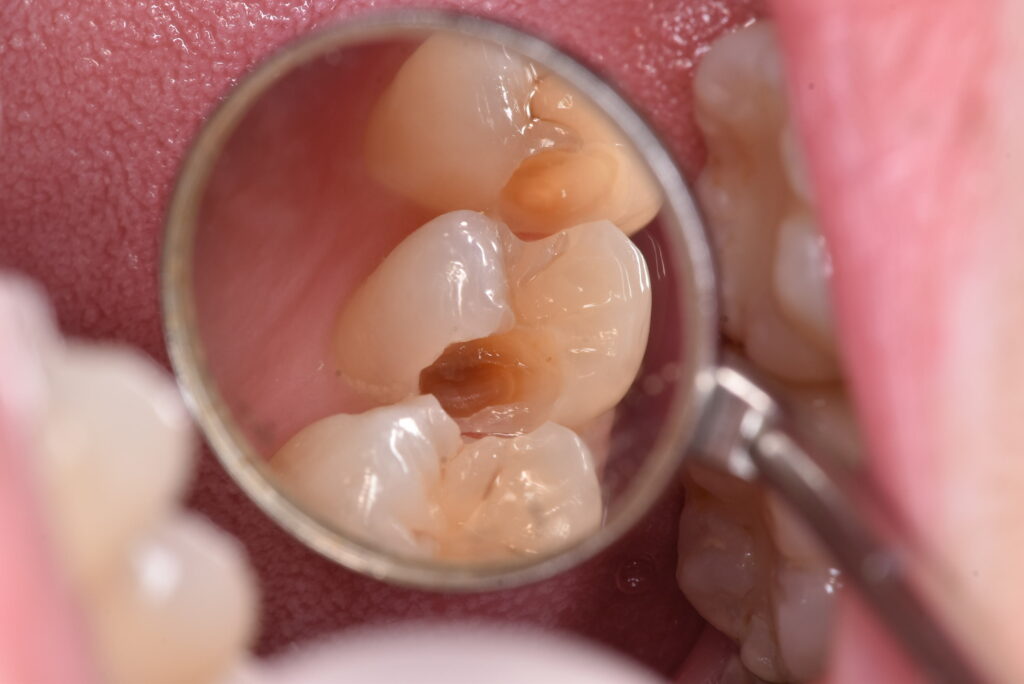

間の部分にむし歯があるのですが、おわかりでしょうか?「なにもないよ!」と言う方の方が多いのではないでしょうか?では、ここを削っていったらどうなったのか、下の写真をご覧ください。

神経に到達する寸前くらいの、深いむし歯が広がっていました。これまでのブログでも書いた通り、今回も症状はありません。では、問題なかったのか?でいうと、答えは上の写真に示した通りです。

上の写真を見返したときに、ご自身がどう感じるか?をよくよくお考え下さい。